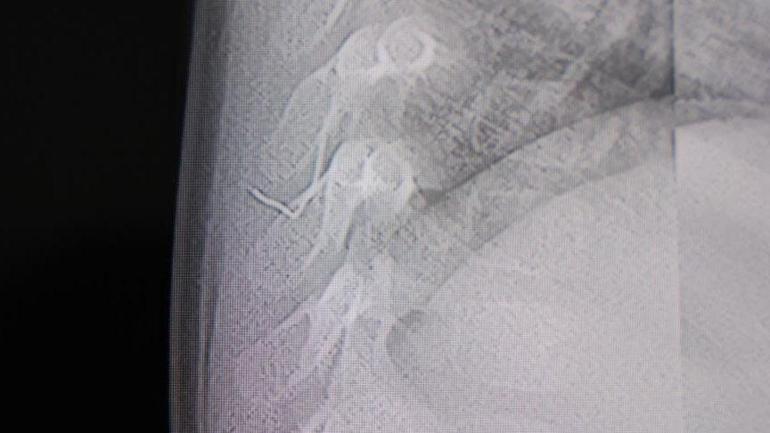

Aile, bebekleri için son olarak Beyin ve Sinir Cerrahisi Uzmanı Prof. Dr. İdris Altun’a götürdü. Prof. Dr. Altun tarafından yapılan tetkiklerde, yabancı cismin cilt altında, omurilik kanalına yakın bir bölgede olduğu ve akciğer zarına doğru ilerlediği belirlendi. Hasta, genel anesteziye alınmadan, lokal anestezi ve sedasyon eşliğinde ameliyata alındı. Yapılan müdahalede yabancı cisim tamamen çıkarıldı. Çıkarılan cismin, ince zımba teline benzer metal bir tel olduğu ve yaklaşık 2 santimetre uzunluğunda bulunduğu tespit edildi. Hasta, aynı gün taburcu edildi.

Konuya ilişkin açıklama yapan Prof. Dr. İdris Altun, “Sırtında yabancı bir cisim olduğu söylenmiş ancak çıkarılamayacağı ve 8 yaşına kadar beklenmesi gerektiği ifade edilmişti. Bize başvurduğunda yaptığımız tetkiklerde, cilt altında, omurilik kanalına çok yakın ve akciğer zarına doğru ilerleyen bir yabancı cisim tespit ettik. Hastamızı tamamen uyutmadan, lokal anestezi ve sedasyon eşliğinde müdahale ederek lezyonu tamamen çıkardık. Çıkardığımız cismin ince zımba teline benzer, yaklaşık 2 santimetre uzunluğunda metal bir tel olduğunu gördük. Bu yabancı cisim alınmasaydı, bölgede enfeksiyon gelişebilirdi. Enfeksiyon sonucu omurilik kanalında ciddi hasarlar oluşabilir, çocuk büyüdükçe cismin hareket etmesine bağlı olarak omurilikte zedelenmeler meydana gelebilirdi. Ayrıca yana doğru ilerleyerek akciğer zarına ve akciğere batma riski vardı. Bu da enfeksiyona ve ilerleyen süreçte tümörle karışabilecek tablolara neden olabilirdi. Şu an hastamız gayet sağlıklı. Gerekli kontrolleri yaptık ve aynı gün taburcu ettik” dedi.